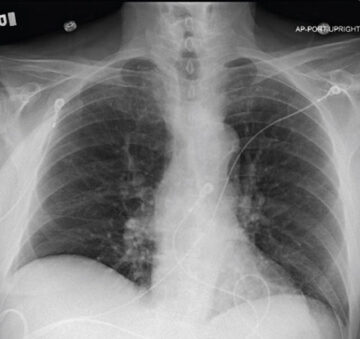

Patient with homogenous emphysema and multiple comorbidities experiencing tremendous improvement in QoL

76 y/o male with homogenous emphysema and multiple comorbidities came off oxygen after treatment (Result not typical)

Successful atelectasis of the right middle lobe with 80% fissure completeness score